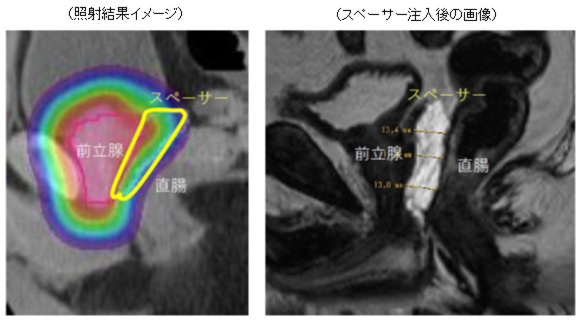

陽子線治療では、放射線は陽子線で照射されます。 X 線との主な違いは、陽子線はエネルギーをターゲットに届けると停止することです。

陽子線治療を使用することで、医師は周囲の組織に損傷を与えるリスクを減らしながら、より正確かつ強力に前立腺がんを標的にすることができます。

ペンシルビームスキャニング陽子線治療を使用すると、医療専門家は陽子線をより広範囲に操作し、集束させることができます。これにより、二重散乱療法よりも正確な線量が得られ、周囲の組織をさらに節約します。

陽子線治療では放射線が集中しているため、通常は従来の放射線治療よりも副作用が少なくなります。それは、腫瘍周囲の健康な組織への損傷が少ないためです。